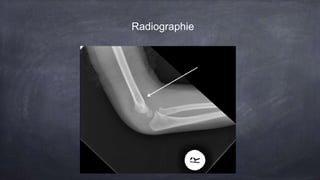

Une fille de 4 ans présente une douleur au coude suite à une chute, ne voulant pas utiliser son bras. Les examens révèlent une douleur à la flexion et une possible fracture, notable par la présence d'un fat pad postérieur sur la radiographie, indiquant une fracture jusqu'à preuve du contraire. Un suivi en orthopédie est recommandé dans les 7 à 10 jours suivant une immobilisation temporaire.